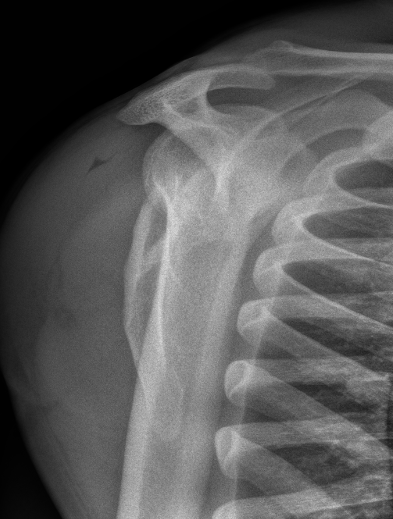

Floating shoulder

Combined scapula body fracture / intra-articular glenoid fracture

Other

- floating shoulder

- combined scapular fracture / intra-articular glenoid fracture